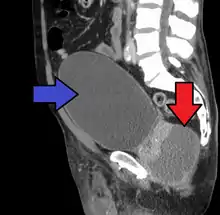

Abscess of the prostate (red arrow) resulting in urinary retention (blue arrow)